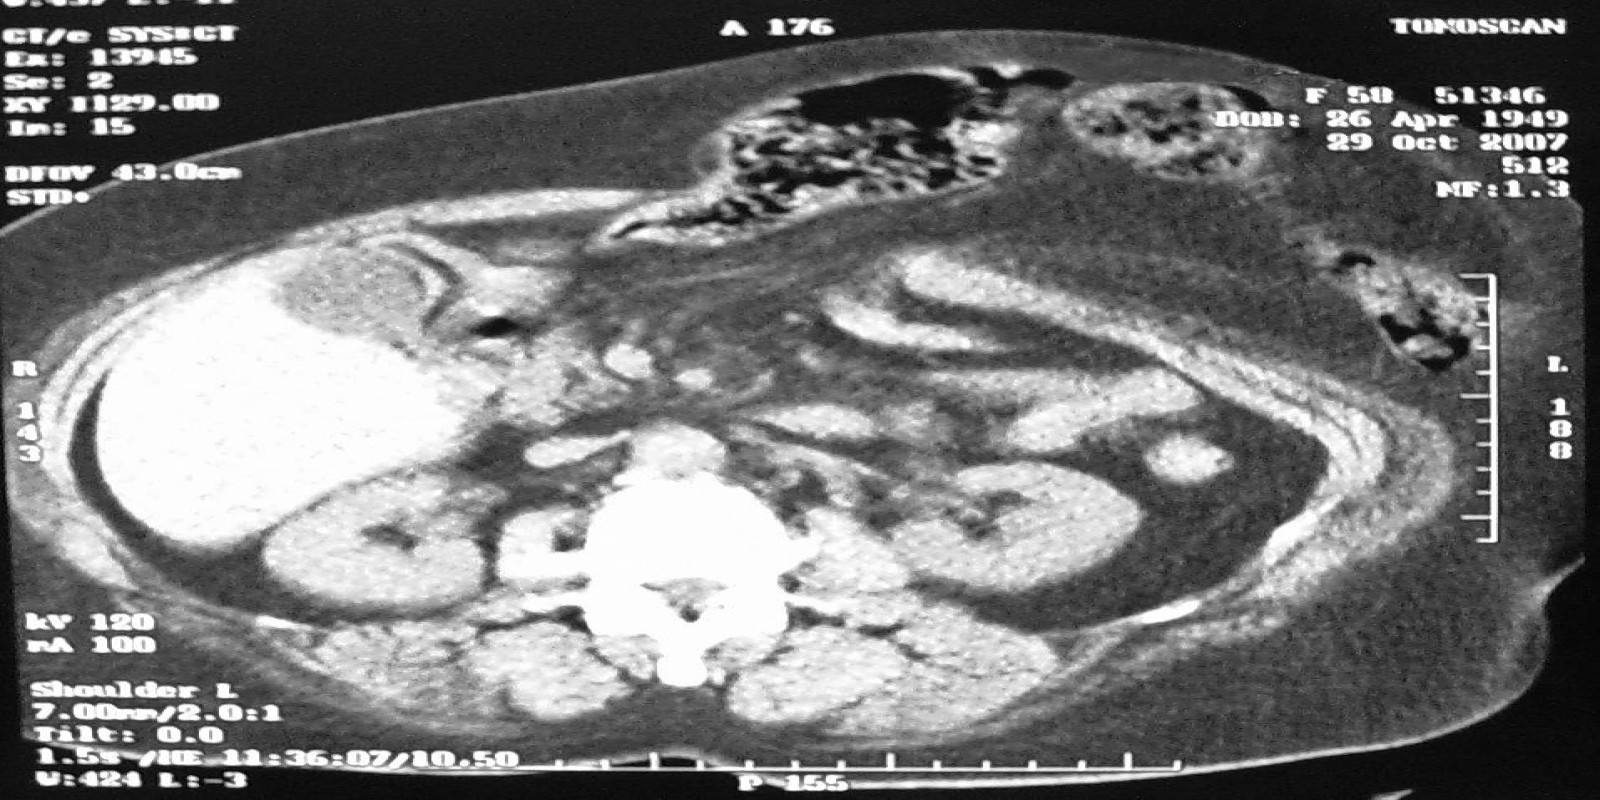

Caso Código 219A de Hérnia Incisional

Cod.: 219A